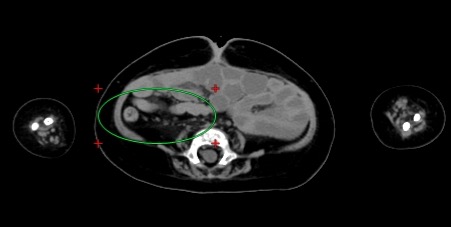

回盲部の周囲のリンパ節が多数認められる

• 胃の噴門部付近に高吸収物あり。出血、その嚥下、薬剤、異物などの可能性を示す。結腸内は内容物に乏しい。小腸内は水様のもので充満。結腸内は虚脱している。直腸から追跡すると S 字結腸は右腹部に主に存在し、長さがかなり長い。十二指腸水平脚の形成が確認されるので腸回転異常の可能性は低いと思われ、また現に腸捻転の状態で はなく、腸管閉塞を疑わせる所見もないが、下行結腸、横行結腸への連続は確実には追求できない。

• 腹水はない。左前腹壁に少量の管腔外のガスがある同部の腹直筋が軽度腫大し、近傍に脂肪混濁があり、皮膚表面に軽度陥没があることから、胃瘻抜去後状態を示しているものか。